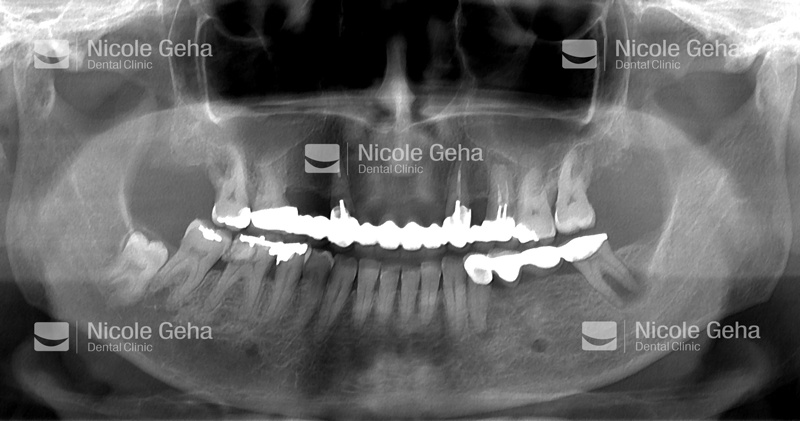

case 1: Before Extraction

case 1: after